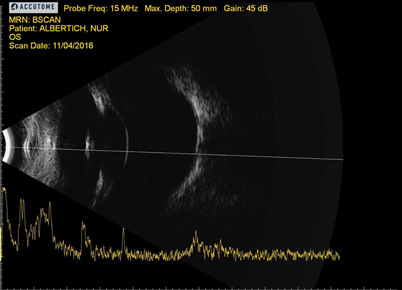

Se realizó una ecografía para descartar otras patologías en el segmento posterior.